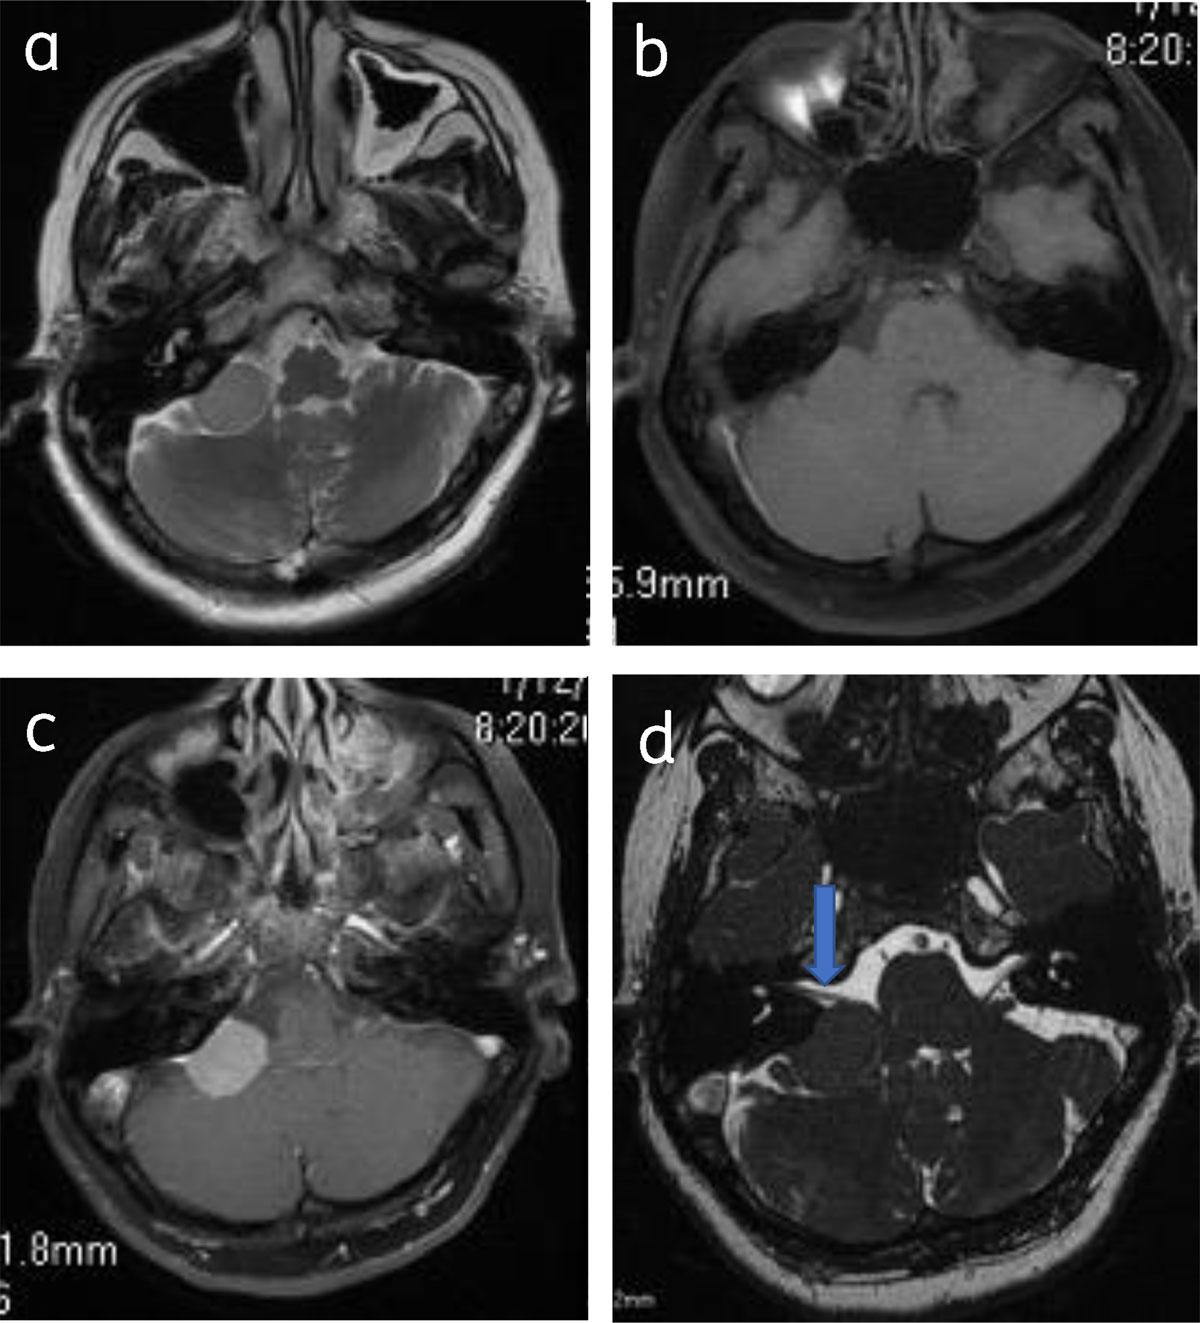

Figure 5

Cerebellopontine angle meningioma: Axial T2 (a), pre-contrast (b) and post contrast (c), show right CPA meningioma with dural tail. Axial 3DFIESTA (d) shows meningioma is indenting right VII–VIIIth nerve complex (arrow).